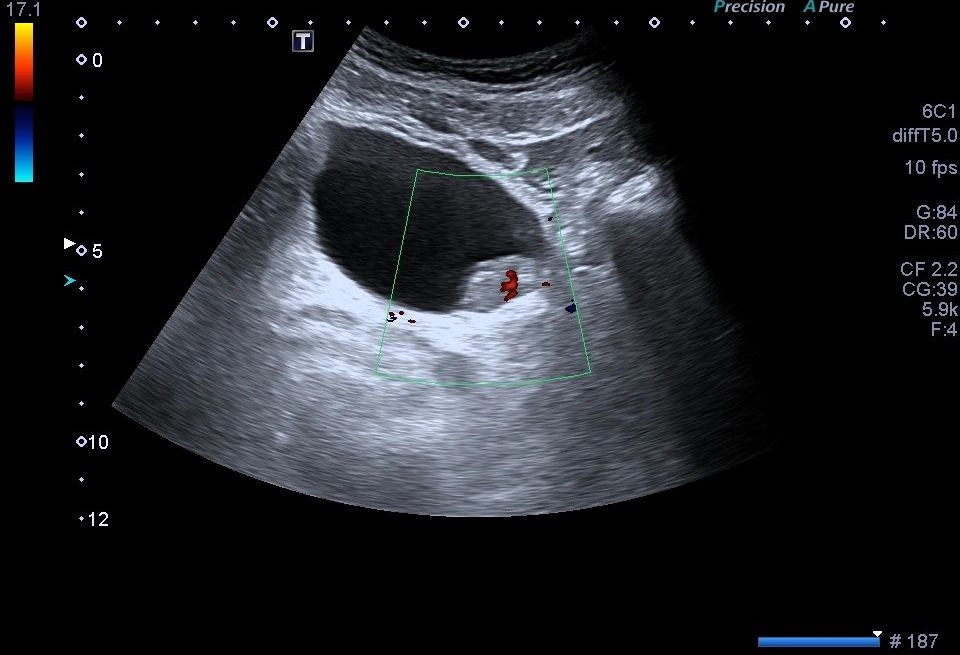

- Vascularización: La evaluación de la vascularización del urotelioma mediante el registro Doppler es crucial. La presencia de flujo sanguíneo dentro de la masa tumoral, representado por colores en el Doppler, sugiere un mayor riesgo de malignidad.

La vascularización es un hallazgo considerado línea roja.

Se recomienda el uso de Doppler Power para detectar vascularización lenta.

Estos hallazgos sugieren la presencia de un tumor y para nosotros, los TSID, es una línea roja.